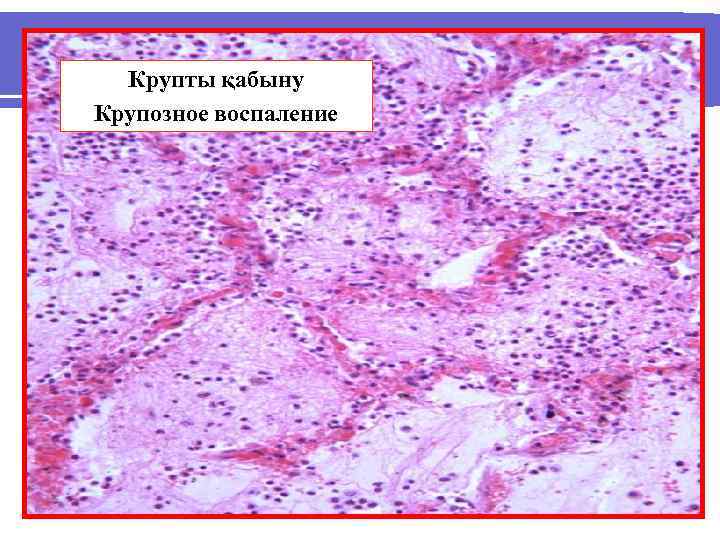

ФИБРИНДІ ҚАБЫНУ – ЭКССУДАТТЫҢ НЕГІЗІН ФИБРИН ЖІПШЕЛЕРІ ҚҰРАП, ҚАБЫРШЫҚ ТҮЗІЛЕДІ. ФИБРИНДІ ҚАБЫНУДЫҢ ТҮРЛЕРІ - КРУПТІ, - ДИФТЕРИТТІ.

КРУПТІ ҚАБЫНУ кезінде фибринді қабыршық түзіліп, ол астындағы құрылыммен тығыз жалғаспайды. Көбіне эпителийі призмапішінді жерлерде дамиды. Фибринді қабыршық түзілген жерлерде шырышты қабықша ұсақ ұнтақ сеуіп қойғандай, бозғылт реңді, ал сірі қабықша түк басқандай, шіпшелі болады. Мысалы, фибринді перикардит - «түкті жүрек» .

Крупты қабыну Крупозное воспаление

Крупты қабыну Крупозное воспаление